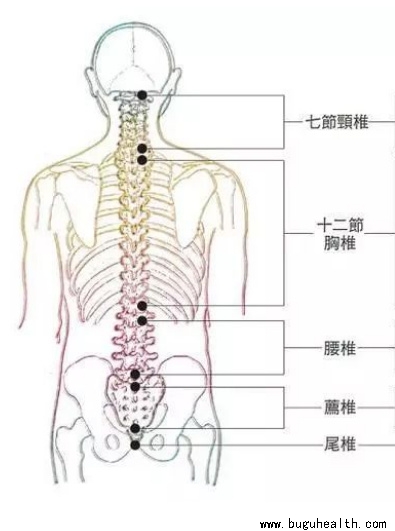

- 脊椎侧弯是一种常见的骨骼问题,在站姿下,不管从正面或背面看,正常的脊椎排列应该是身体左右两边对称,并且正常的脊椎排列从上到下是呈一直线的。.....

- 布骨医学科普:脊柱侧弯的康复功能锻炼方法! BuGuRMC布骨康复医疗中心 ,2023-06-26

- 脊柱侧弯是非常常见的一个问题,那么,如何简单的判断一个人是否有脊柱侧弯呢?如果你患有背部疼痛或轻度脊柱侧弯,或者你想预防脊柱侧弯,请开始下面的练习。.....